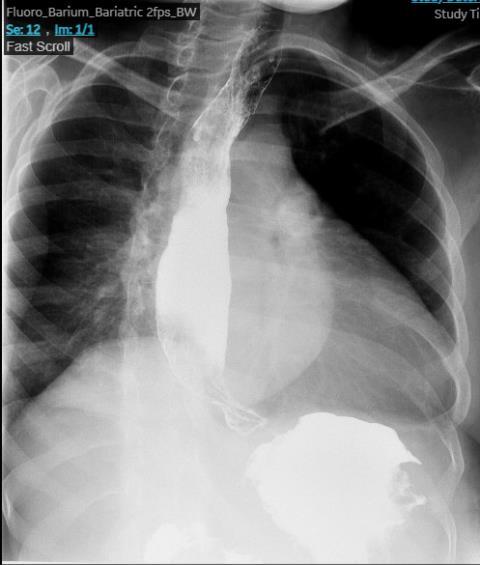

BURKITT LYMPHOMA INDUCED PSEUDOACHALASIA WITH DRAMATIC SYMPTOMATIC IMPROVEMENT POST-CHEMOTHERAPY

Marni H. Wilkoff1 , Emily S. Seltzer1 , Allison E. Wang1,2 , Bruno Almeida Costa1 , Bruce Gelman1

1Mount Sinai Morningside-West Hospitals, Icahn School of Medicine at Mount Sinai, New York, NY, United States;

2Mount Sinai Beth Israel Hospital, Icahn School of Medicine at Mount Sinai, New York, NY, United States 69